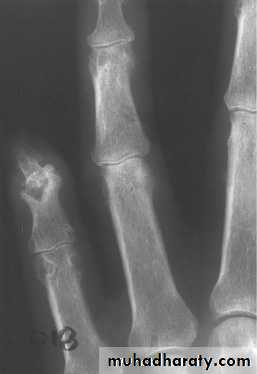

Radiographs are often normal during early episodes of gout. They may be useful to differentiate other problems such as fracture or infection from acute gout. Often, soft tissue swelling is the sole radiographic finding in early gout.

In the later stages of untreated disease, clinical manifestations characteristically change. Acute attacks are more often polyarticular. The intercritical stage shortens, and repeated joint damage results in permanent deformities, loss of motion, chronic pain, and tophi.

Tophi are deposits of urate embedded in a matrix composed of amorphous urates, lipids, proteins, and calcific debris . Tophi are usually subcutaneous, but they rarely occur in bone and other organs including the heart valves and the eye.